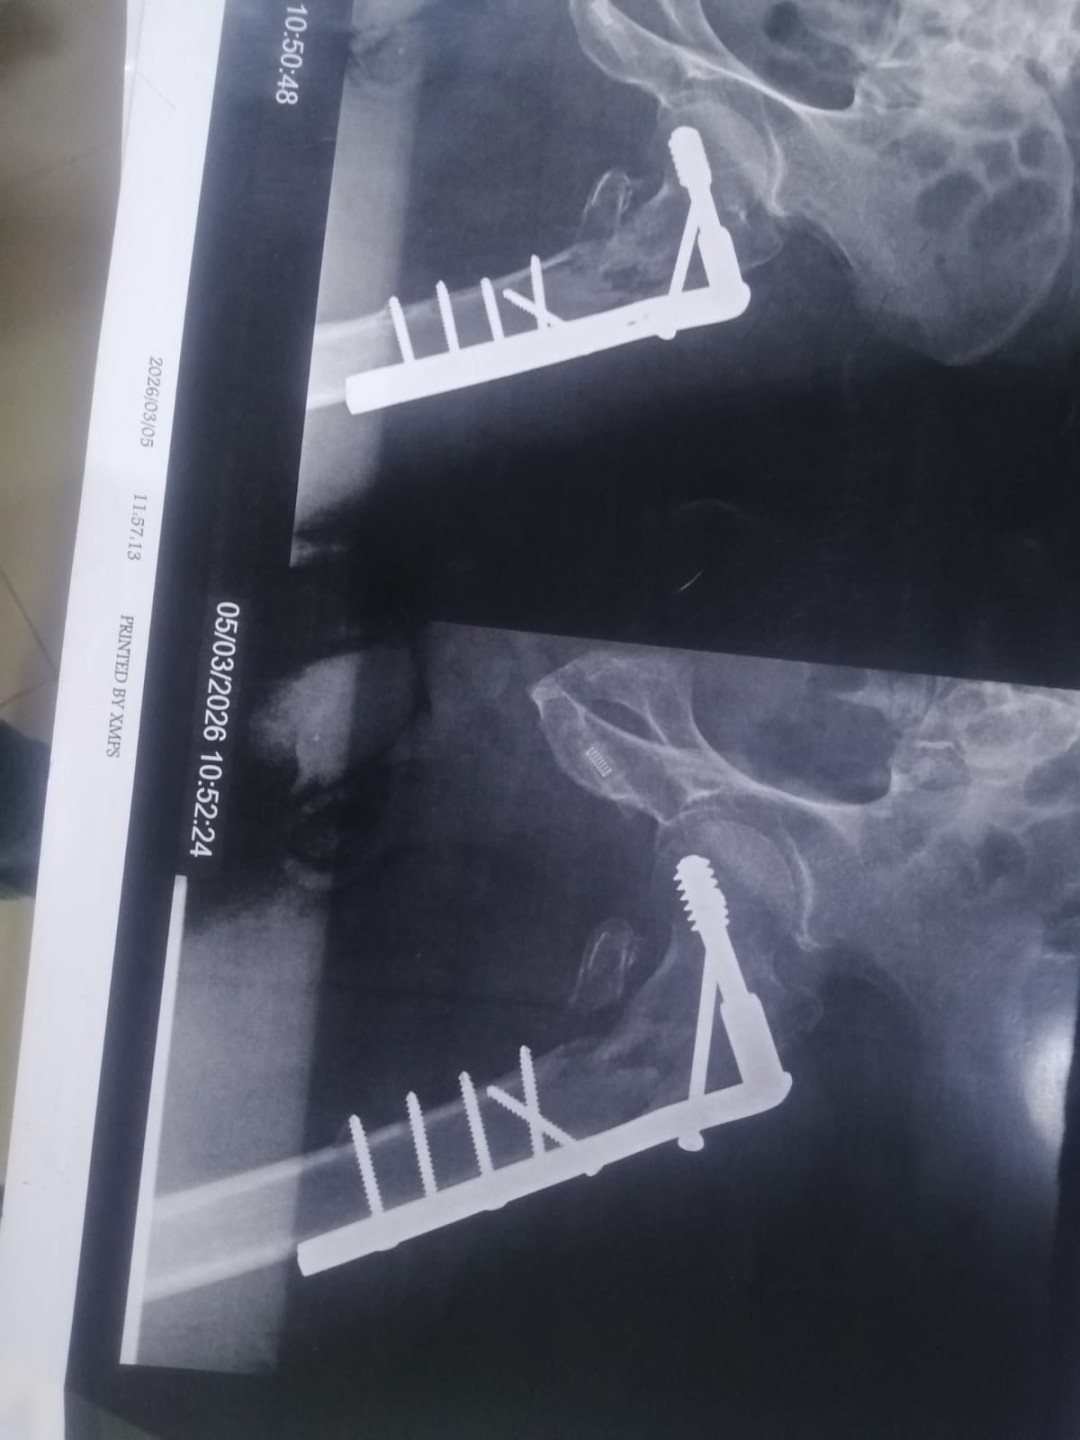

جاءت الحالة الأولى، لمريض يبلغ من العمر 80 عامًا وصل إلى المستشفى يعاني من كسر معقد بمفصل الفخذ حيث تم حجزه بالعناية المركزة وتجهيزه بالكامل لإجراء التدخل الجراحي، وبعد استقرار حالته تم دخوله غرفة العمليات وإجراء جراحة دقيقة لتصليح الكسر وتركيب شريحة ومسامير وتكللت العملية بالنجاح وتم نقل المريض من العناية المركزة إلى القسم الداخلي حتى تحسنت حالته وخرج من المستشفى بحالة جيدة

أجرى العملية فريق طبي ضم الدكتور علي أحمد، أخصائي جراحة العظام ، والدكتور أحمد مجدي ، نائب العظام ، والدكتور محمد الأنصاري، استشاري التخدير، بمشاركة فريق تمريض العمليات وذلك تحت إشراف الدكتور أسامة رشاد، رئيس قسم جراحة العظام

كما نجح الفريق الطبي ، في إجراء عملية مماثلة لمريض يعاني من كسر معقد بمفصل الفخذ حيث تم تصليح الكسر وتركيب شريحة ومسامير وتكللت العملية بالنجاح وغادر المريض المستشفى بحالة صحية جيدة

وضم الفريق الطبي الدكتور محمد سلمي، أخصائي جراحة العظام ، والدكتور رؤوف، نائب العظام ، والدكتور مينا لوقا ، طبيب التخدير، بمشاركة فريق تمريض العمليات